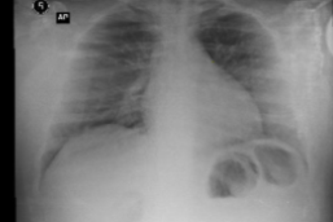

x ray and ct covid-19 model detect